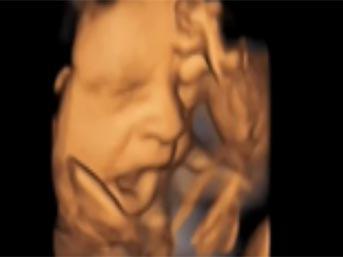

Bebeğin esneme anı

Bebeğin esneme anı galerisi resim 5